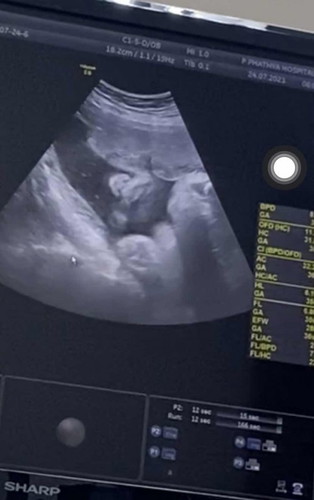

มีใครแตกไปแล้วบ้างคะ บ้านนี้ยังไม่มีทีท่าว่าจะแตกเลย แต่ดิ้นหนักหน่วงมากเลยค่ะ เริ่มลงต่ำทุกวันๆแล้ว ปวดๆหายๆบริเวณช่วงจิ้มิ้ บ้านนี้กำหนดคลอด 25 สิงหา อยากแตกแล้วค่ะ น้ำหนักแม่ขึ้นมา 7 โลแล้ว น้องได้ 2808 #ท้องแรกคะ